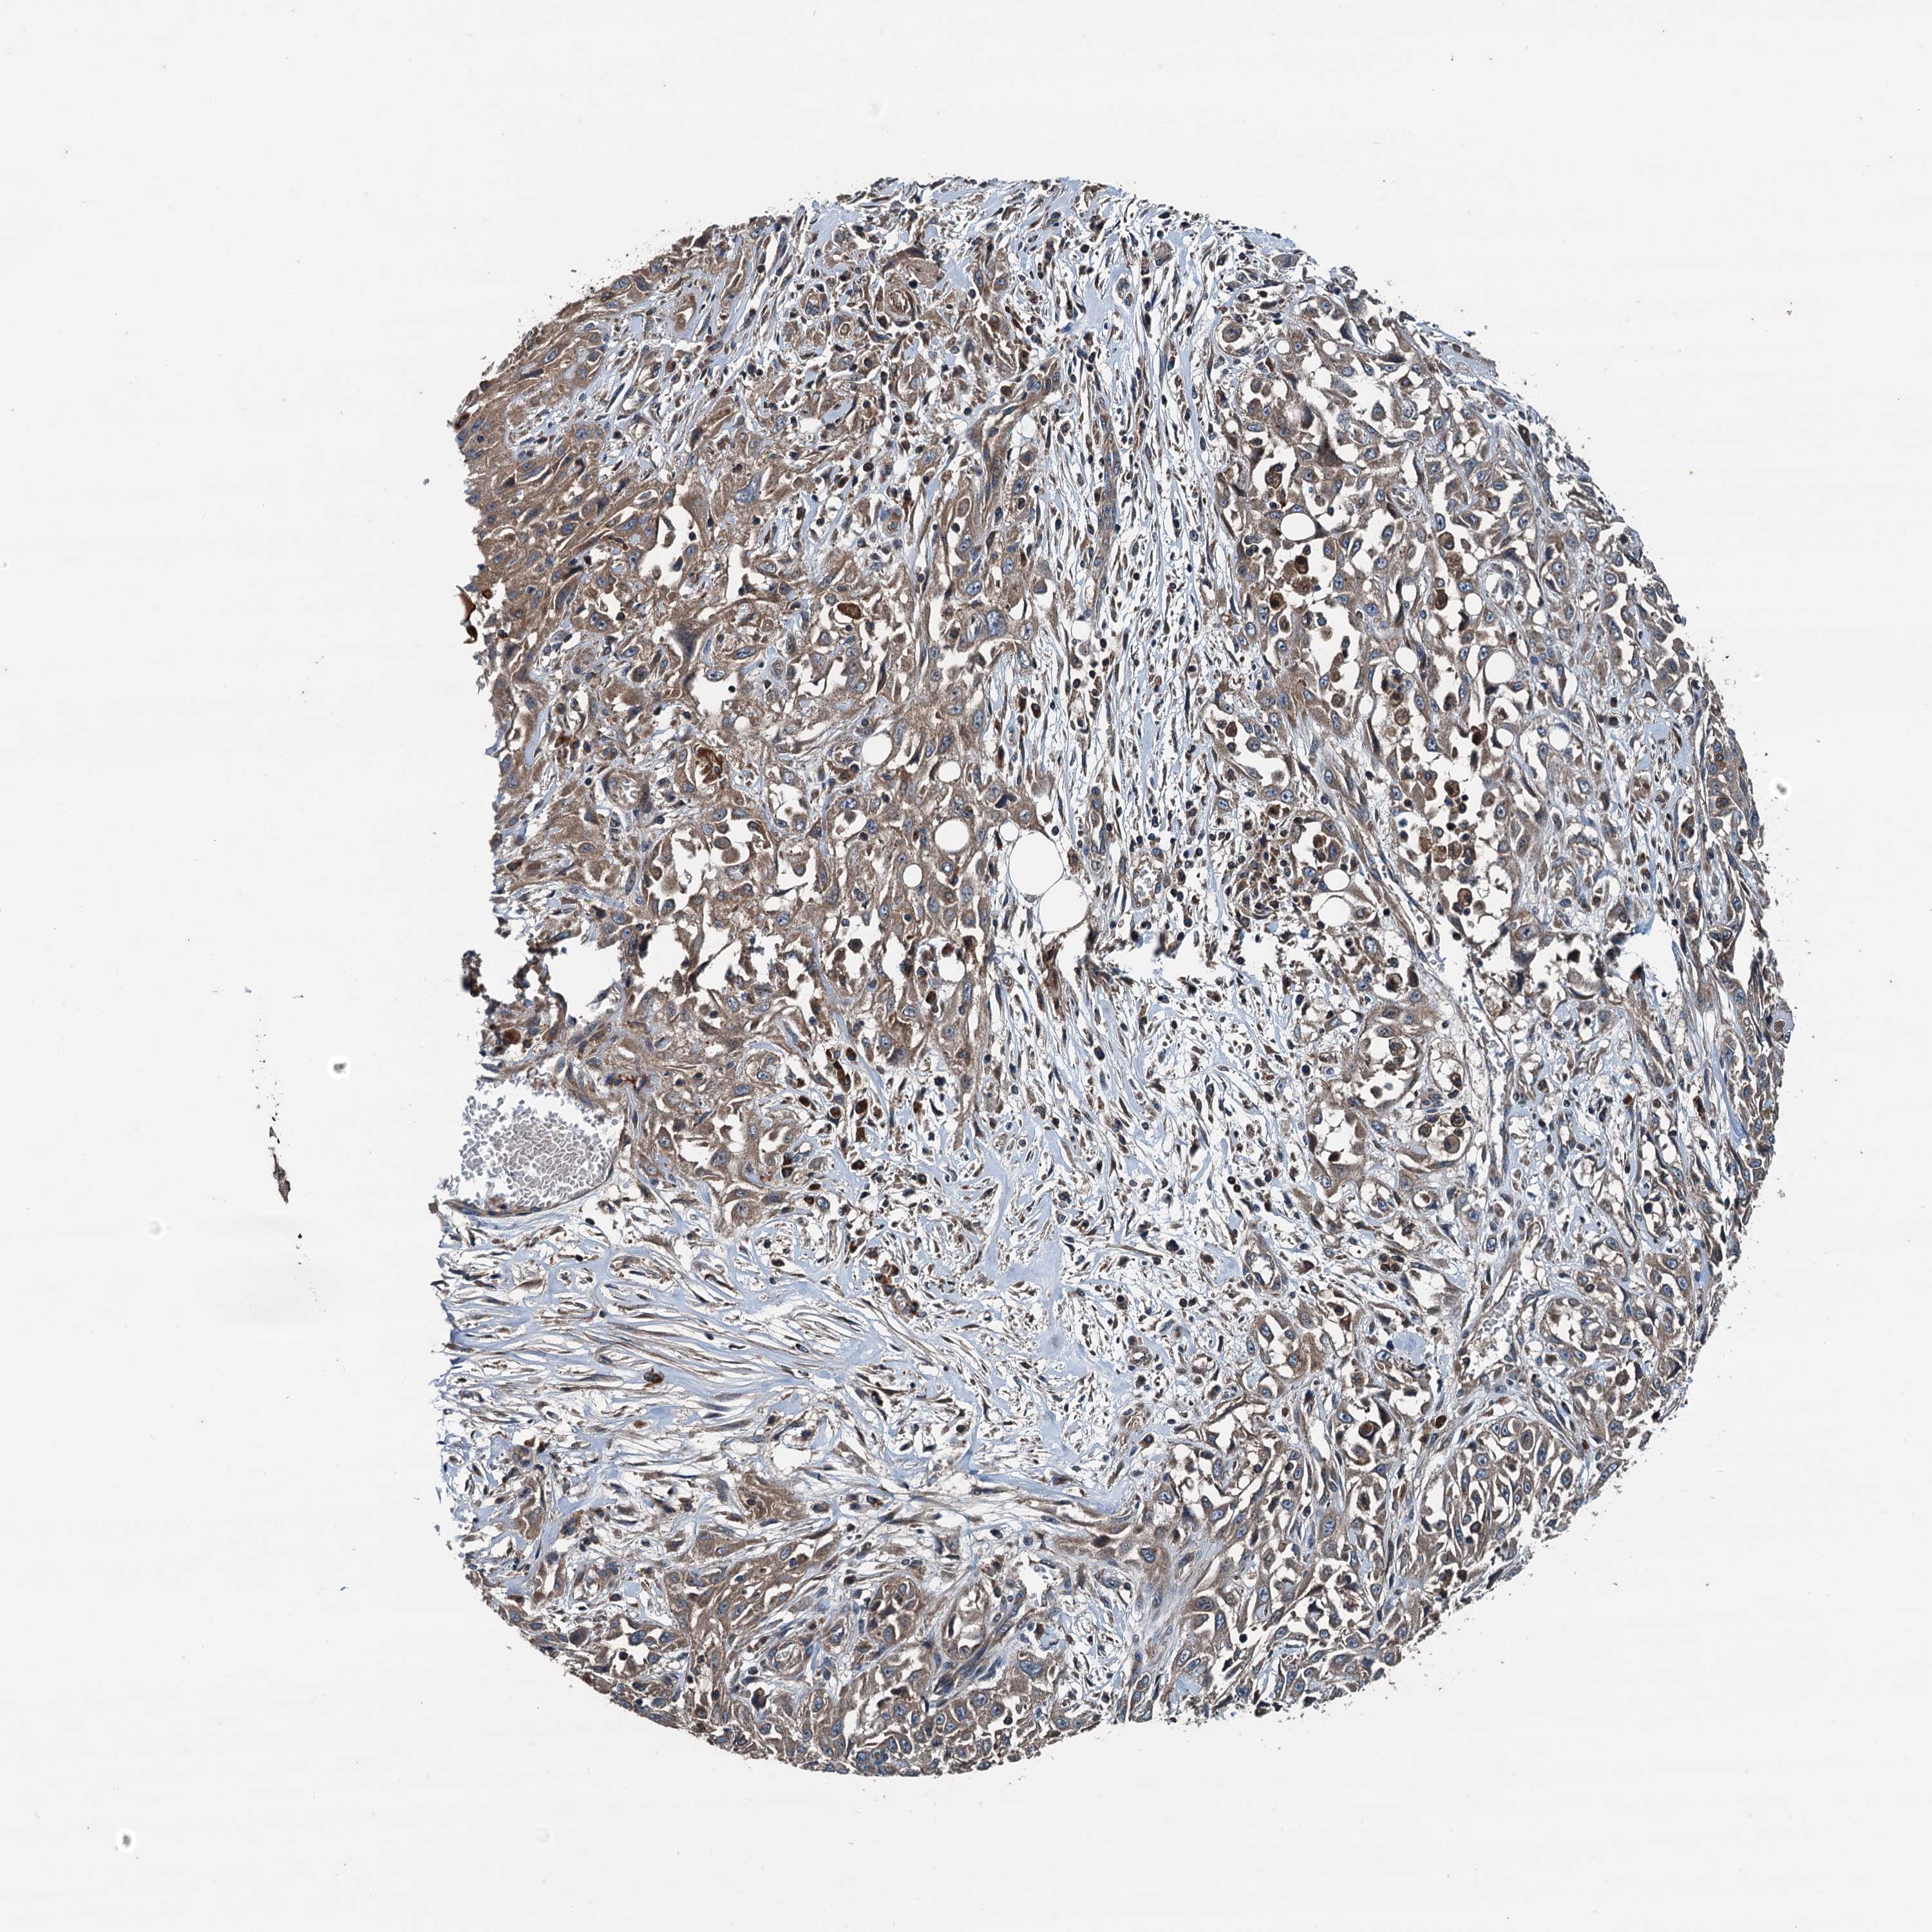

SKIN CANCER - Protein expressioni

A mouse-over function shows sample information and annotation data. Click on an image to view it in a full screen mode. Samples can be filtered based on level of antibody staining by selecting one or several of the following categories: high, medium, low and not detected. The assay and annotation is described here.

Antibody stainingi

Antibody staining in the annotated cell types in the current human tissue is reported as not detected, low, medium, or high, based on conventional immunohistochemistry profiling in selected tissues. This score is based on the combination of the staining intensity and fraction of stained cells.

Each image is clickable and will lead to virtual microscopy that enables deeper exploration of all samples and also displays staining intensity scores, fraction scores and subcellular localization as well as patient and tissue information for each sample.

Antibody HPA041227

Staining

High

Intensity

Strong

Quantity

>75%

Location

Nuclear

Basal cell carcinoma

Squamous cell carcinoma, NOS

Squamous cell carcinoma, metastatic, NOS